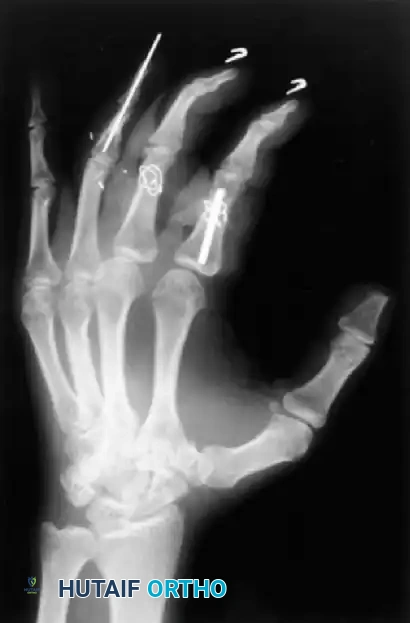

Fig. 64-4 A and B, Open fractures of right hand with loss of distal end of middle phalanx and painful small fi nger partial amputation. C and D, Proximal phalanx of painful and stiff small fi nger was used as structural graft to restore articular column of middle fi nger.

Figure 64-4: Massive Trauma and Reconstructive Efforts.

A and B, Severe open fractures of the right hand demonstrating loss of the distal end of the middle phalanx and a painful, partially amputated small finger. C and D, Innovative reconstructive salvage: The proximal phalanx of the painful and stiff small finger was harvested and utilized as a structural bone graft to restore the articular column and length of the middle finger.